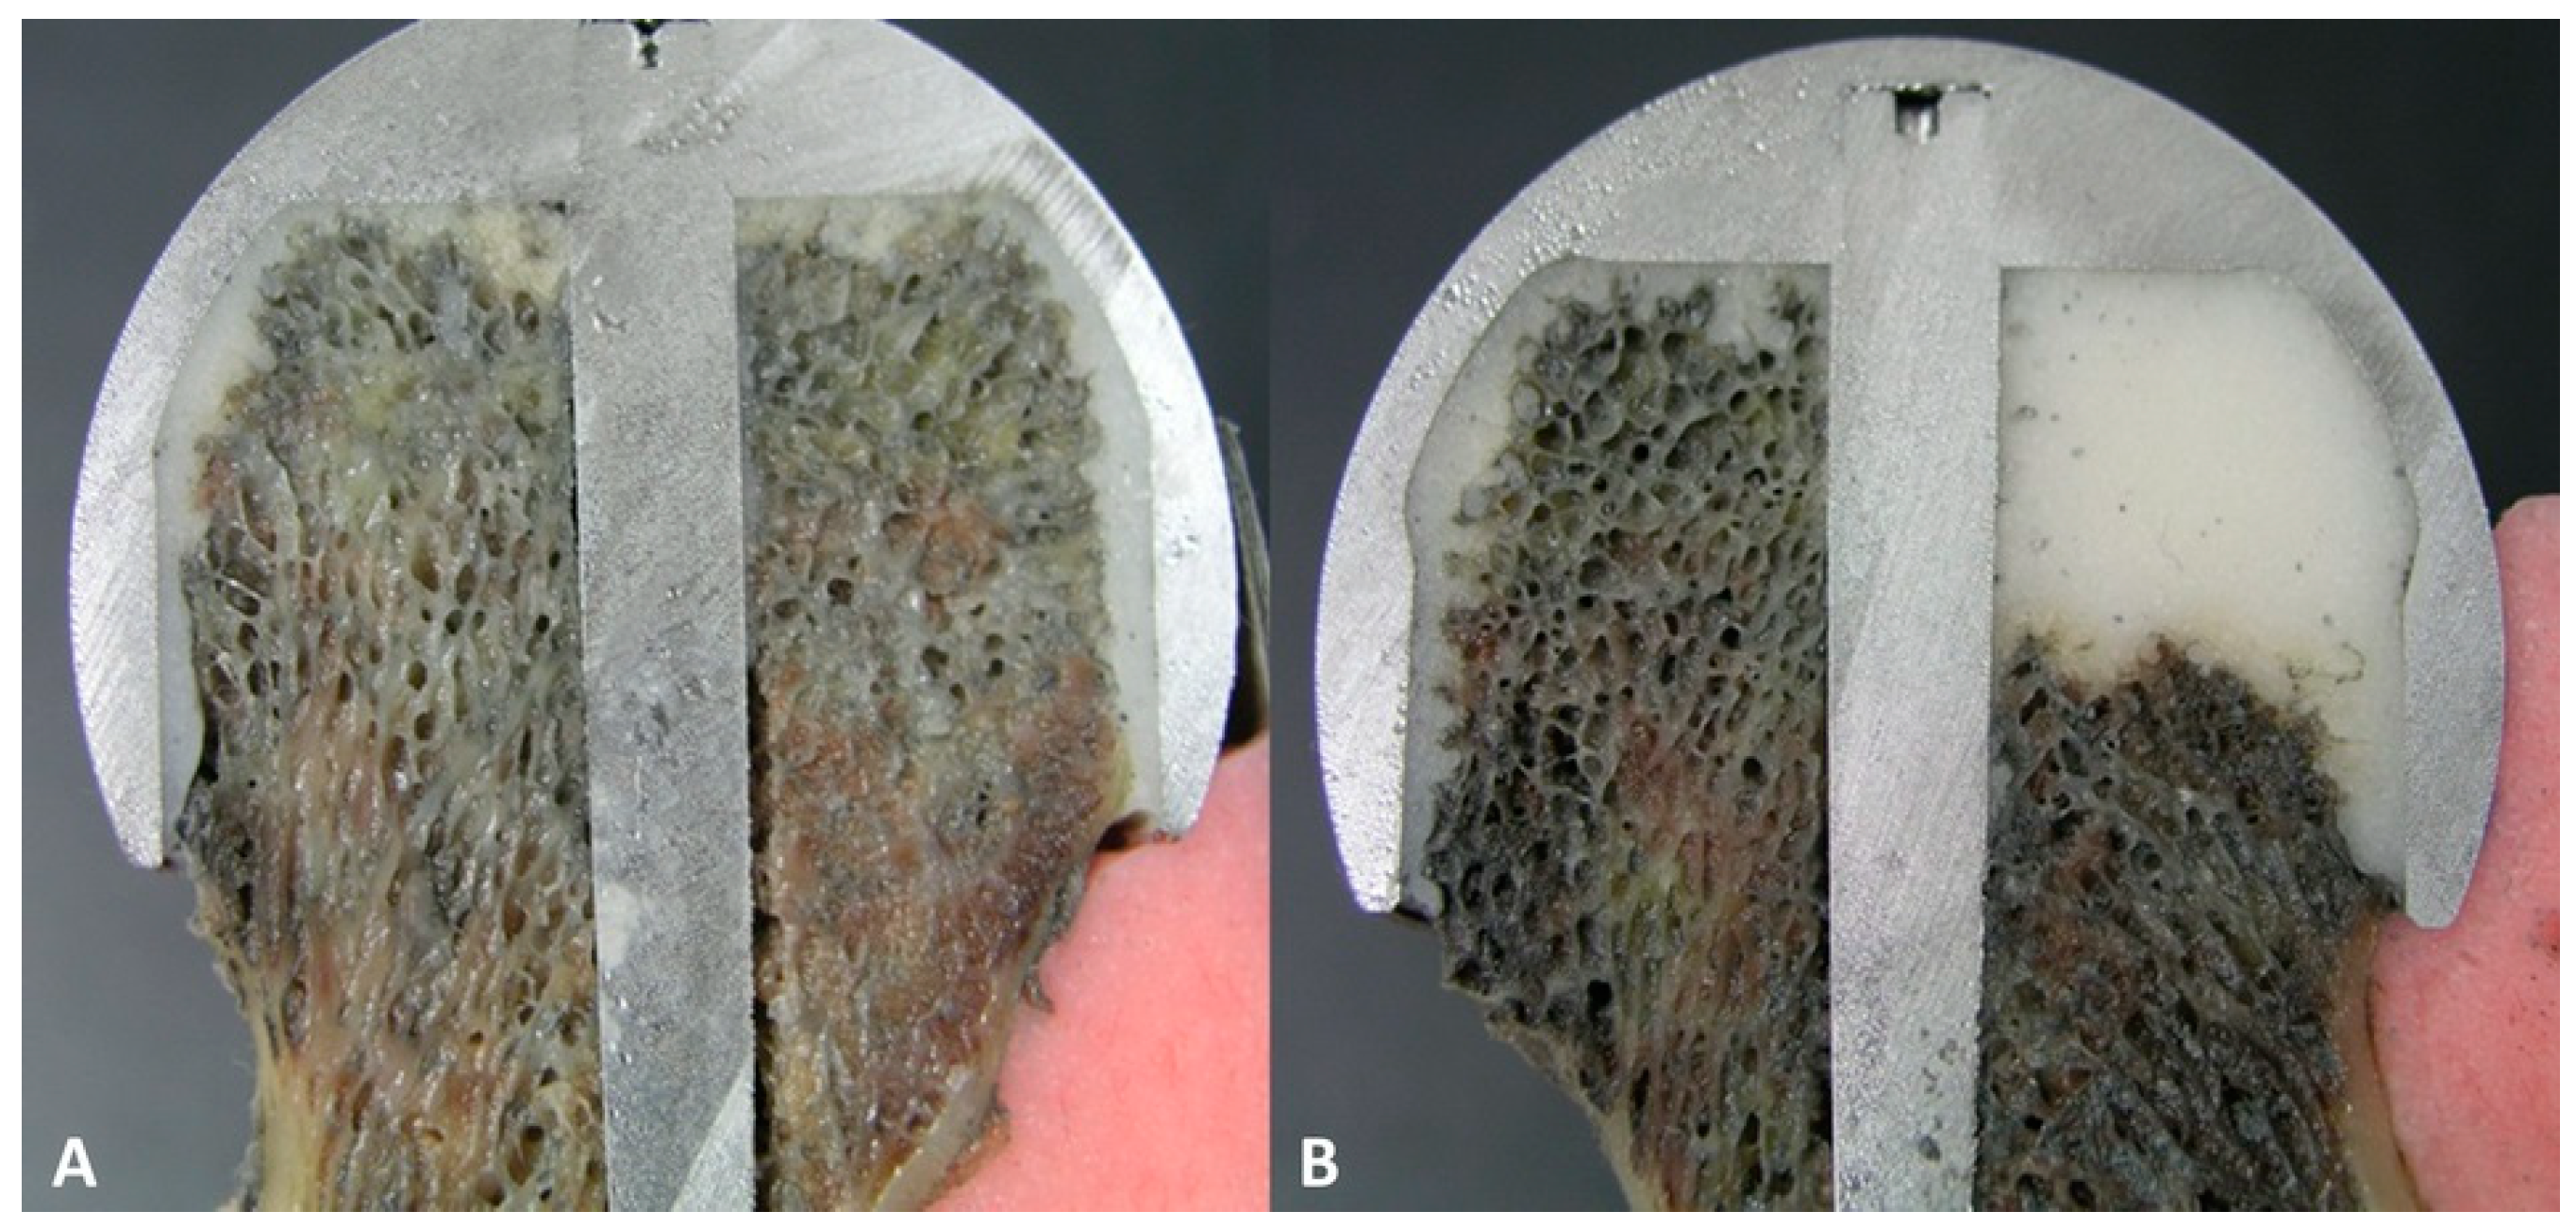

2.4. Scanning Electron Microscopy (SEM)

3.3. The Bond Strength at the Bone–Cement Interface